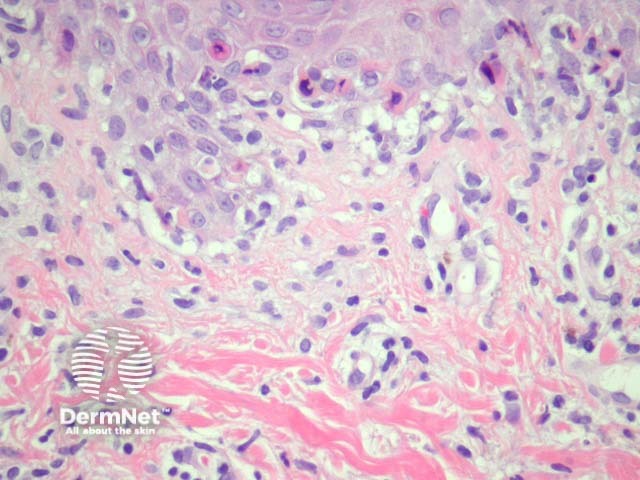

Sections usually show acral skin with a lymphocytic infiltrate which infiltrates the epidermis (figure 1). The infiltrate is associated with keratinocyte apoptosis in early lesions (figure 2). Figure 3 shows a high power view of a more established lesions: there is papillary dermal oedema (lower half of the field), epidermal necrosis, dyskeratosis, and intraepidermal vesiculation as a consequence of epidermal oedema.

Figure 3